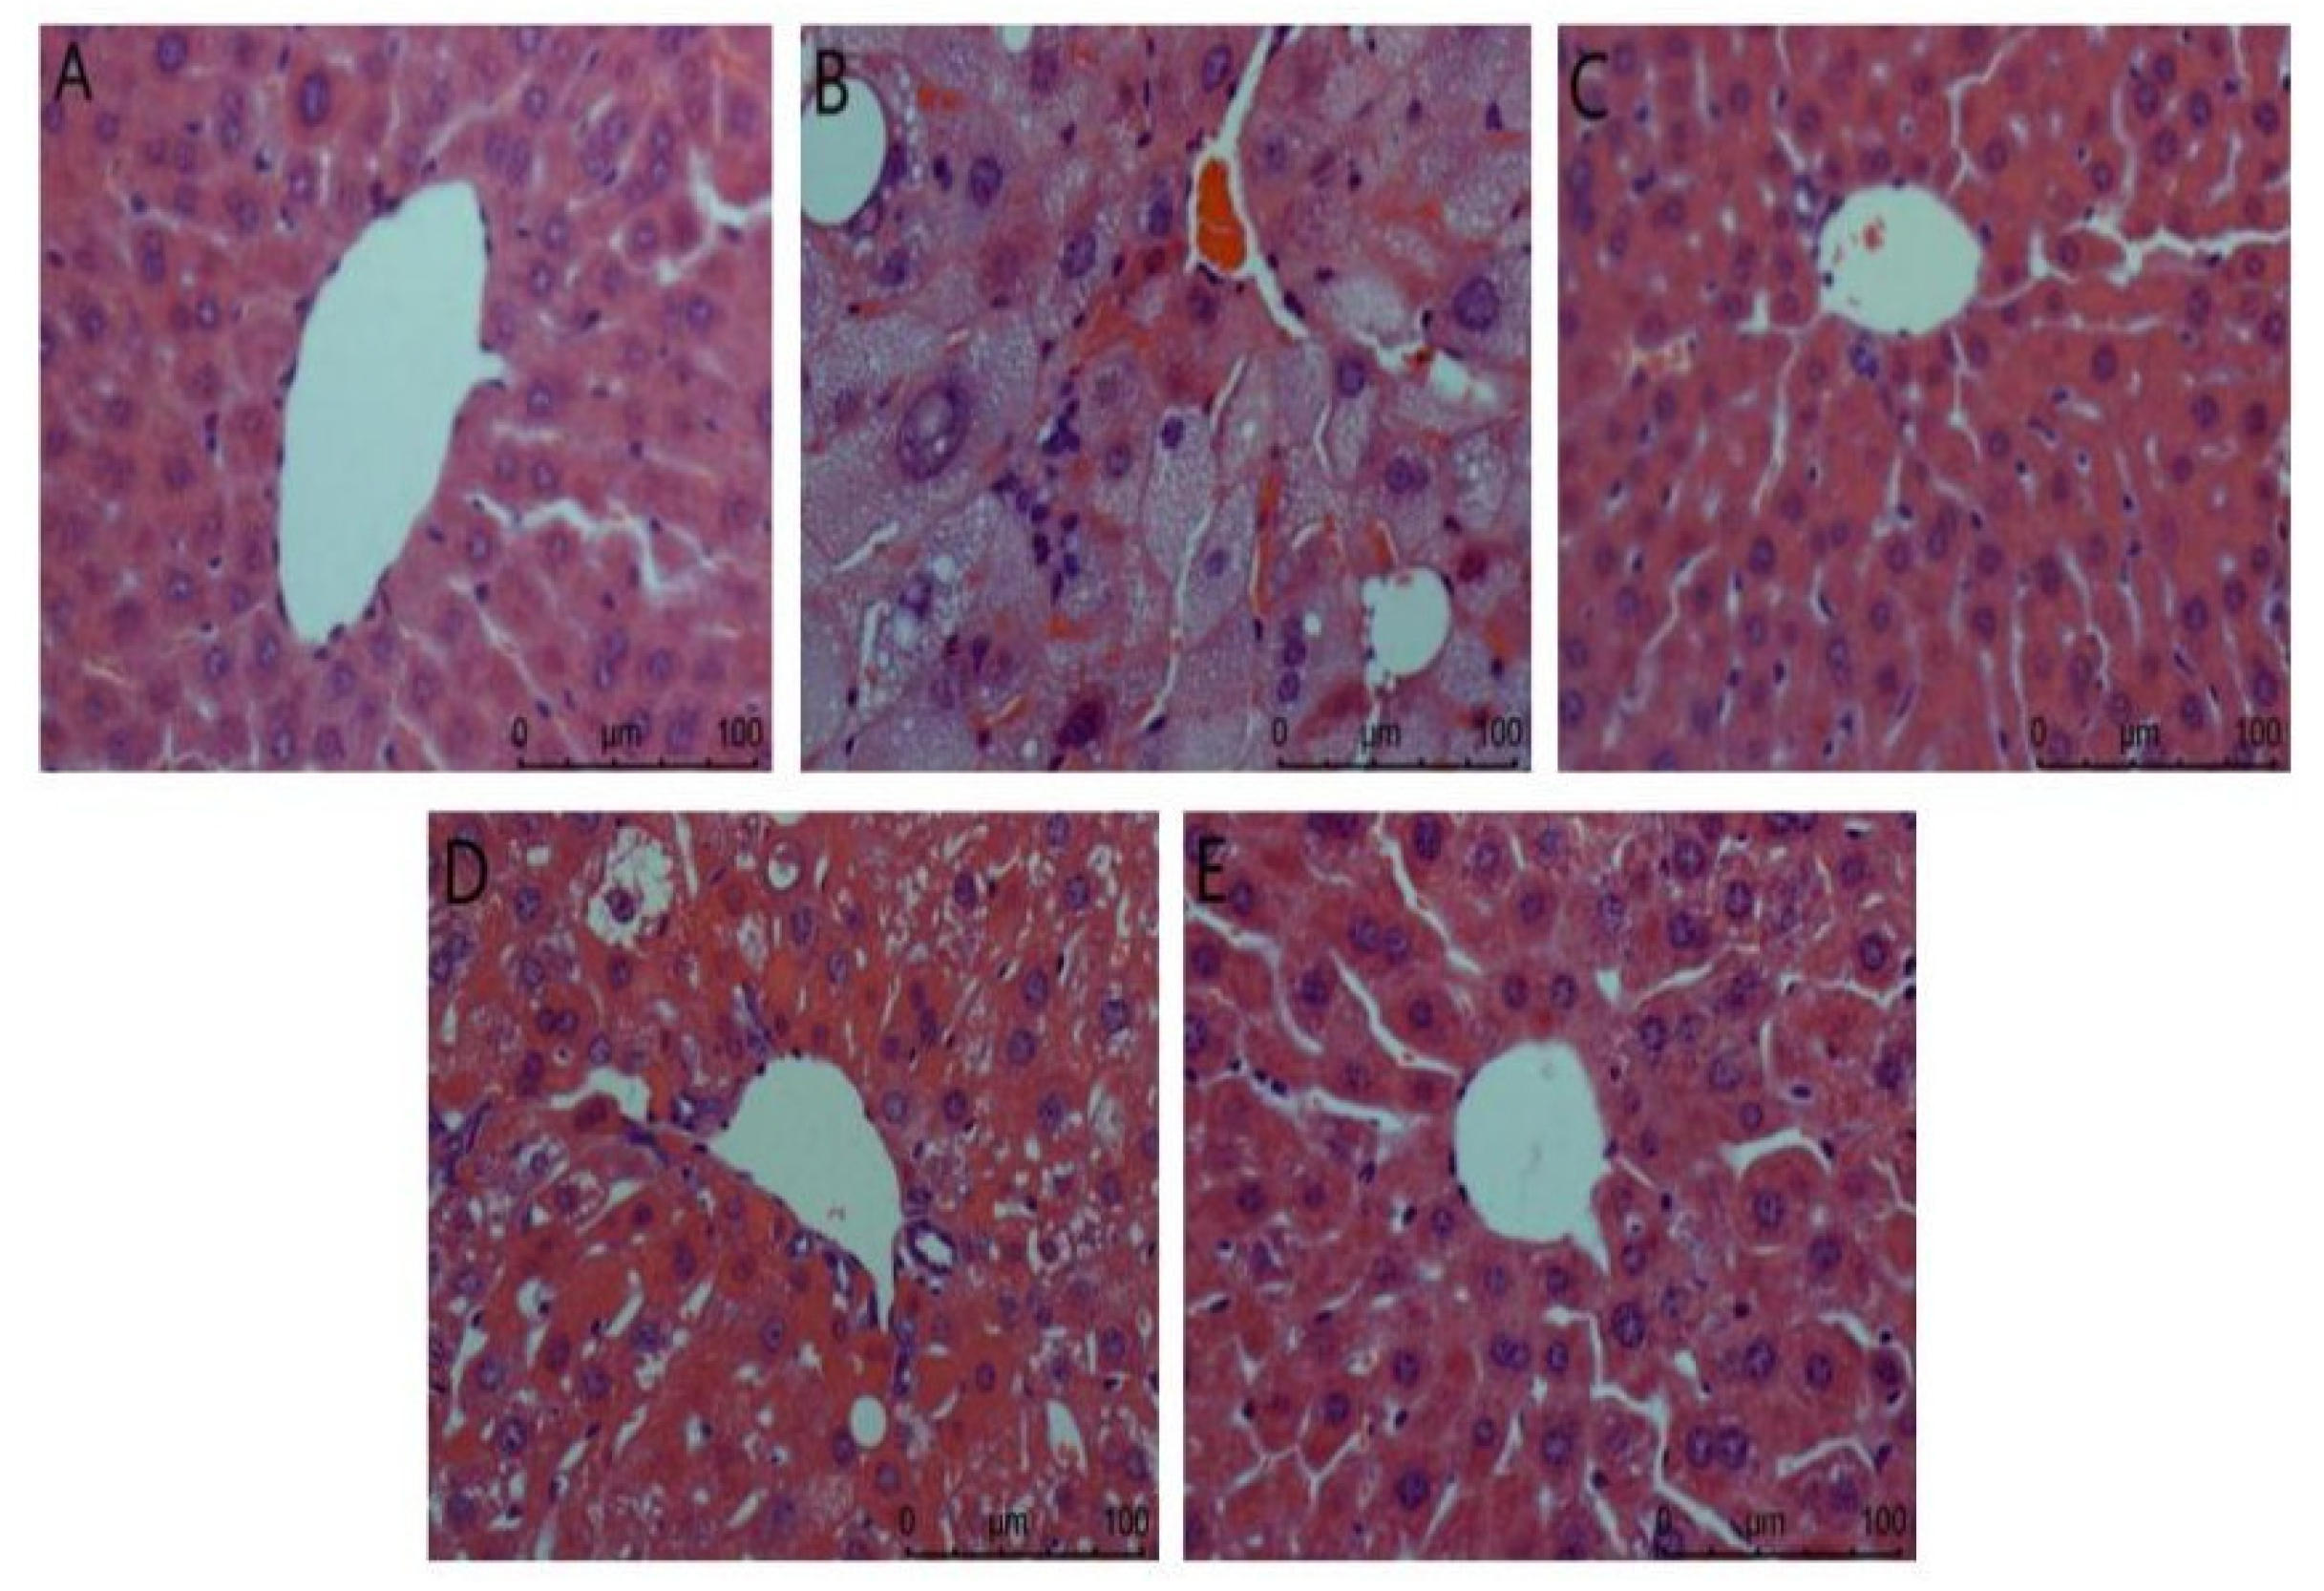

3.4.2. Effects of ACP on Organs of DM II Mice

- (2)

- Kidney